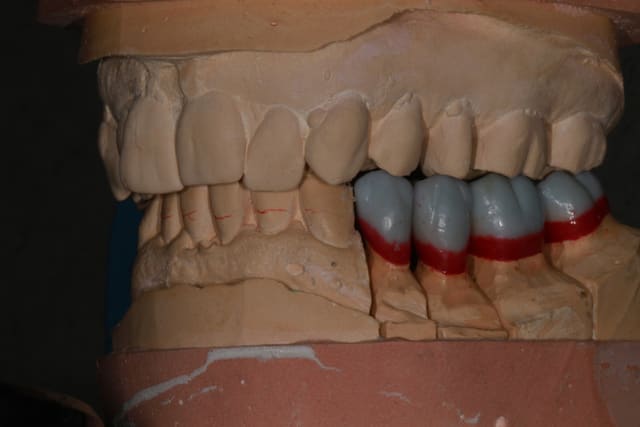

25/09/2013 à 22h10

Wax up et taille crayon...

Empreinte, détourage et préparation des cires avec une occlusion différente de celle du wax up, un peu plus de DV

Le trait rouge sur les incisive donne à peu de chose prêt l'origine...